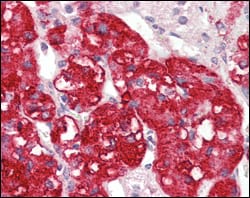

Product Image

- Immunohistochemical analysis of paraffin-embedded human ovary carcinoma (A), normal cerebrum tissues (B), breast infiltrating carcinoma (C) and breast infiltrating carcinoma (D), showing cytoplasmic localization using STYK1/NOK mouse mAb with DAB staining.

- Immunohistochemical analysis of paraffin-embedded human adrenal tissues using STYK1/NOK mouse mAb with DAB staining.